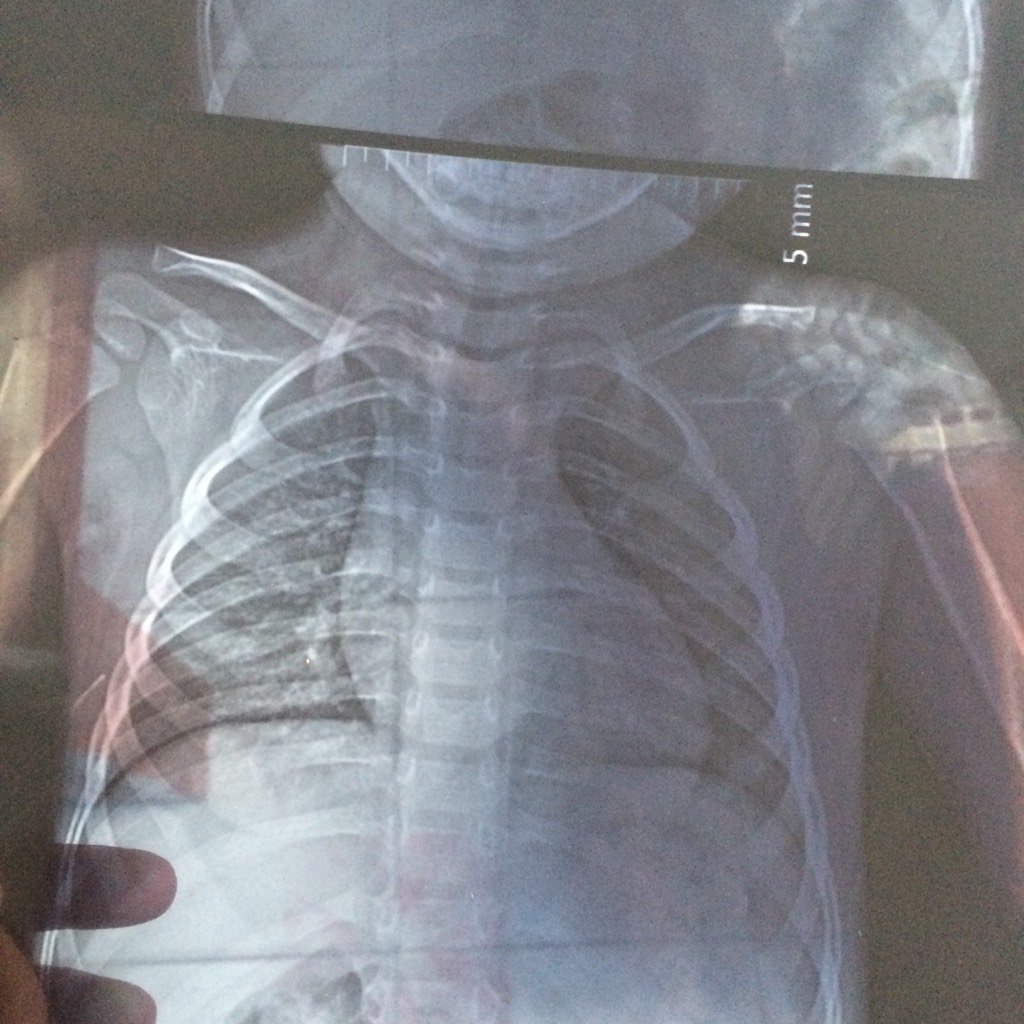

锁骨骨折,谁能帮我看看厉害吗?好怕锁骨错位,畸形,影响到美观,才两岁的宝宝 锁骨骨折,谁能帮我看看厉害吗?好怕锁骨错位,畸形,影响到美观,才两岁的宝宝 点击展开 159*****915_SvYJ 2016-10-07 13:40 为您推荐: 其他回答 前臂最好是吊起来了,不用固定要3周左右时间 zhixuping1 2016-10-08 09:49 没事!!! 雪娃娃_LKRq 2016-10-07 14:08 大乳房里面膜 小卖酸菜鱼 2016-10-07 13:51 看上去还可以,应该属于不完全性骨折,预后良好,不会有什么畸形。 zhixuping1 2016-10-07 13:45 相关问题 锁骨骨折以后长错位了怎么办 小孩锁骨骨折10天复查有错位,不想做手术是否有保守治疗方案 3岁小孩锁骨骨折断端错位,软组织肿胀,请问需要手术吗